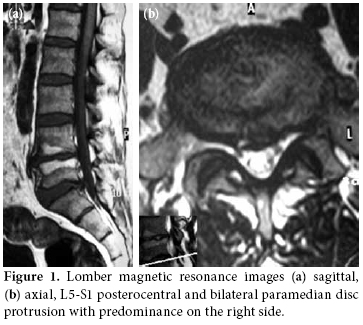

A 49-year-old man complained of pain and swelling of the feet and ankles, particularly on the left side. Two months previously, he had experienced an episode of low back pain radiating down the left leg which developed after an episode of bending and lifting. At that time, he was diagnosed with LDH which was confirmed by magnetic resonance (MR) imaging. The lumbar spine MR images showed L5-S1 disc protrusion in the posterocentral region and in bilateral paramedian regions which was more apparent on the right side (Figure 1). His pain decreased after several days of bed rest and analgesic treatment. One month later low back pain, aching and stiffness developed in the joints of both ankles and feet and was accompanied by dorsal hyperalgesia and allodynia of the left foot. The aching was exacerbated by local pressure or attempted foot movement. Over the next month the symptoms steadily worsened to the point of an inability to bear any weight on the right foot. Mild swelling of the feet, edema, and hyperhydrosis of the left foot were also noted. Ankle motion was restricted near the end of range. There was a complaint of low back discomfort. Straight leg raising on the left side was only 45 degrees. There was a suggestion of mild plantar flexor weakness (4/5, 0 to 5 scale) on the left, but extreme pain on palpation of the left lower extremity prevented reliable motor strength and sensorial evaluation. The remainder of the neuromuscular examination was unremarkable. Rectal tone was intact, and pulses were normal. The patient had no history of trauma. Past medical history, family history and a review of systems were unremarkable revealing no indication of endocrine, rheumatologic or other systemic diseases.